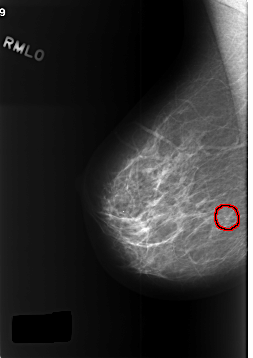

C_0381_1.RIGHT_MLO

FILE: C_0381_1.RIGHT_MLO.OVERLAY

TOTAL_ABNORMALITIES 1

ABNORMALITY 1

LESION_TYPE CALCIFICATION TYPE AMORPHOUS DISTRIBUTION CLUSTERED

ASSESSMENT 4

SUBTLETY 5

PATHOLOGY BENIGN

TOTAL_OUTLINES 1

BOUNDARY